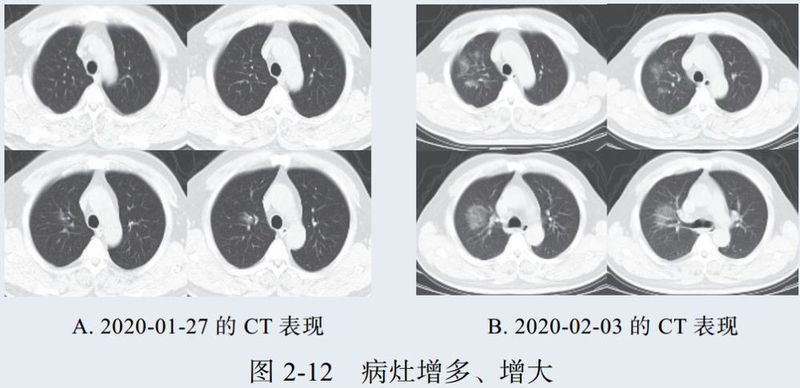

二、进展期征象

新冠肺炎大多数病例进展迅速,复查 CT 影像发生明显变化。

表现为病灶数目明显增多,范围明显扩大,密度增高,病灶分布由外周向中央推进。

根据既往 SARS 病理学机制,提示为肺泡腔内聚集大量细胞渗出液、间质内血管扩张渗出;肺泡连通起来形成融合态势(图 2-11)。

图 2-11 病灶数目增多、范围扩大 (A-D)